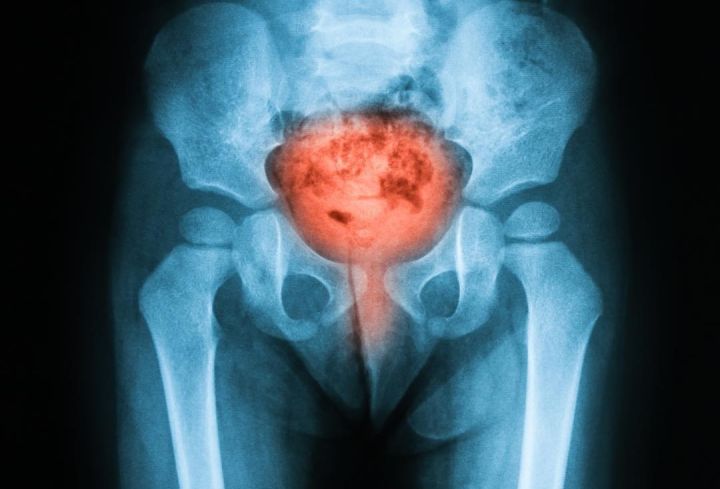

一老年旅客在飞机上突然无法排尿,当时同在机上的张红和肖占祥2名医生经过诊断:老人膀胱大致存有1000毫升尿液,如不尽快排出,则会面临膀胱破裂的危险。

憋尿中的膀胱就会像被堵住出气口的气球,内壁受到的压力越来越大,为了能容纳更多的尿液,膀胱壁会因膨胀变薄。

膀胱膨胀、收缩、再膨胀、再收缩的过程,长期反复,造成的后果就是:要么失去弹性,那么断裂。

➤憋尿膀胱会爆炸吗?

有可能!

还有一种可能就是在膀胱憋尿的时候,受到外力,就更加容易爆炸。

- 此时,你觉得还可以继续憋,直到膀胱里的尿液达到「警戒值」——800cc。